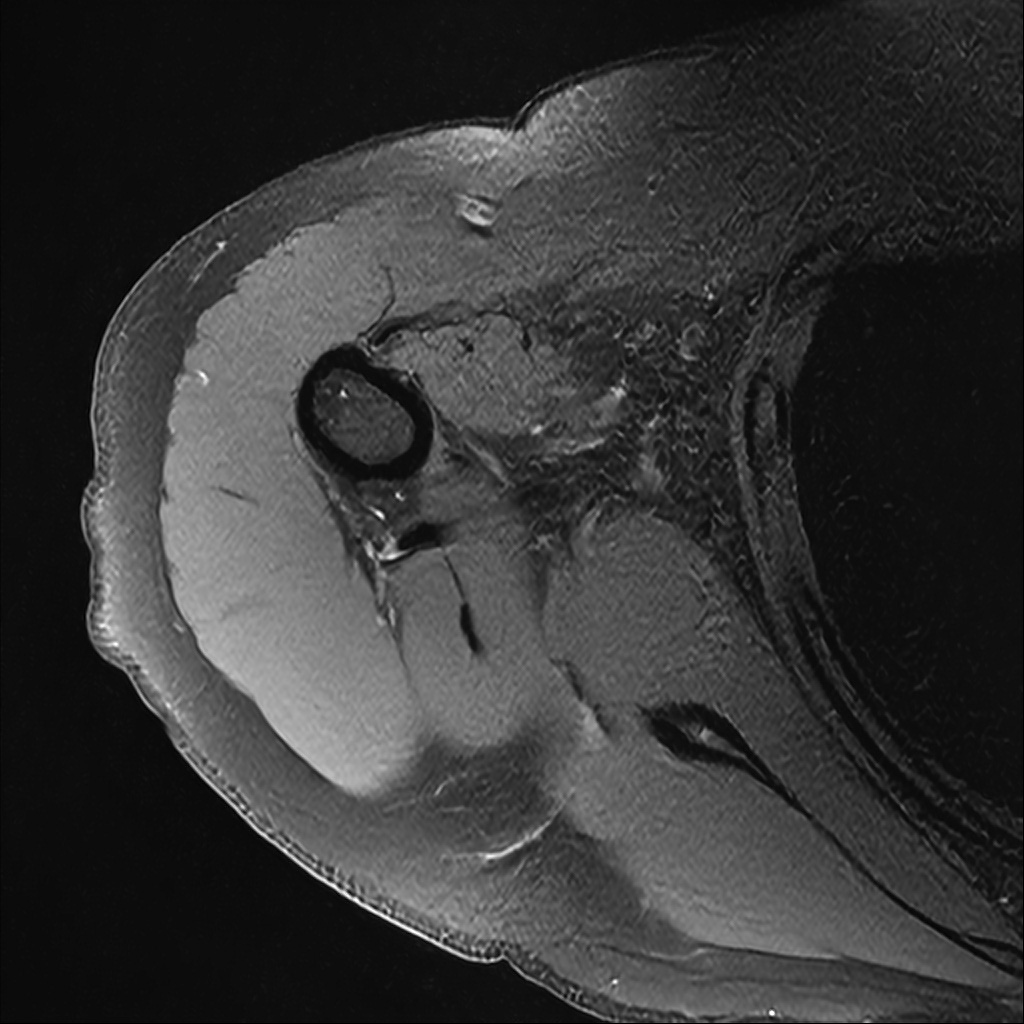

Mri 단면 영상으로 보아 어깨 관절 부위에서 이상 신호가 관찰되고 이는 관절 와순 파열의 가능성을 시사할 수 있습니다.

하지만 이영상만으로 정확한 진단은 불가능하고 정밀한 판단을 위해선 전체 시퀀스와 영상의학과 전문의의 공식판독이 필요합니다 특히 와순 파열은 위치와 동반 병변에 따라 해석이 달라집니다!